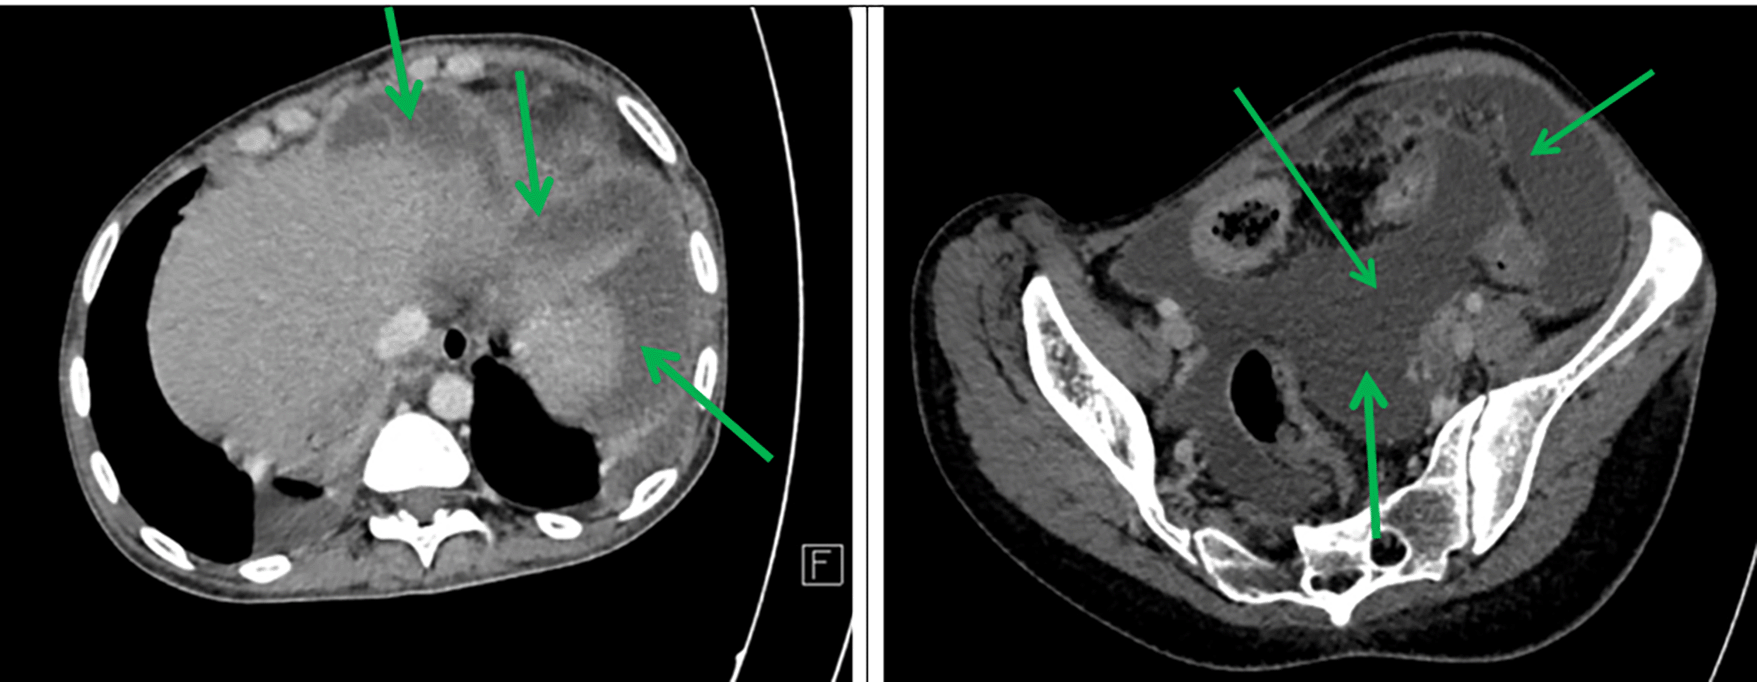

Axial sections taken at portal time after injection of contrast agent showed abundant intra-peritoneal effusion ( Figure 2).